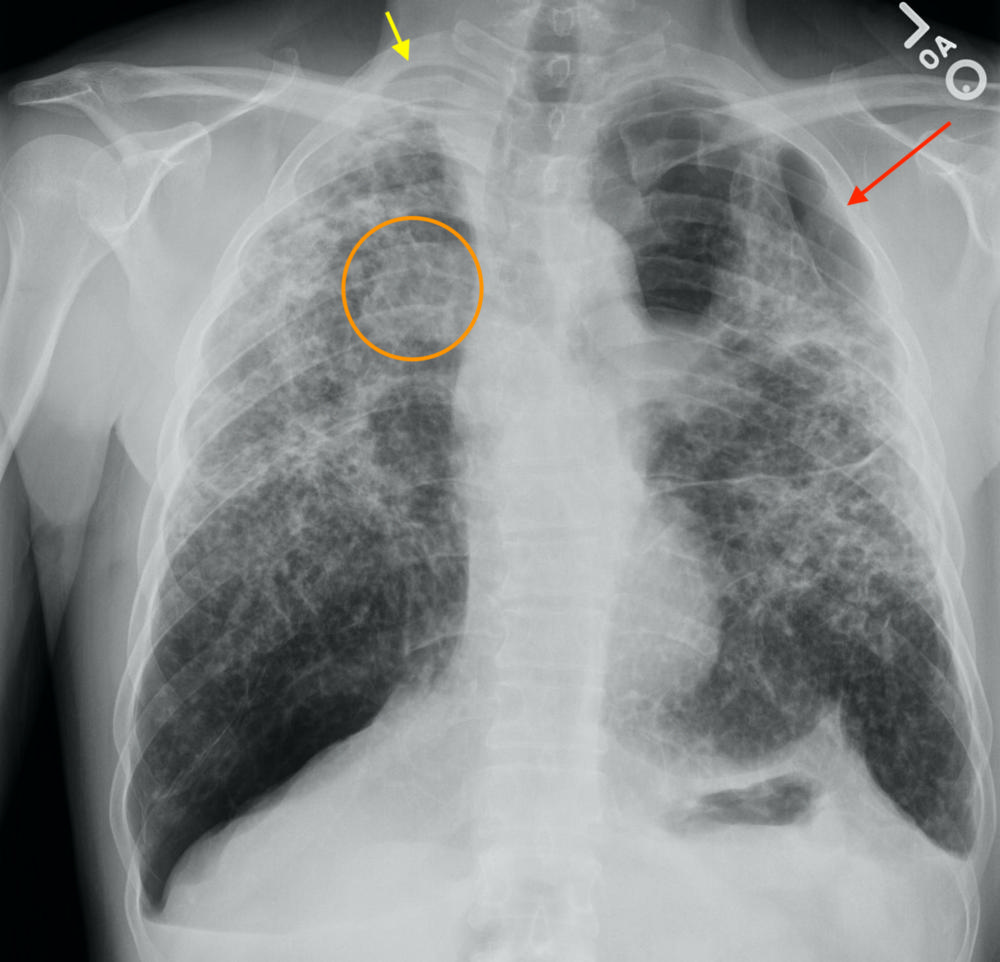

Figure 1. Chest x-ray with a left-sided tension pneumothorax (lung collapse - red arrow), with flattening of the diaphragm (orange arrow) and shift of the mediastinal structures, including the heart and airways (yellow arrow).